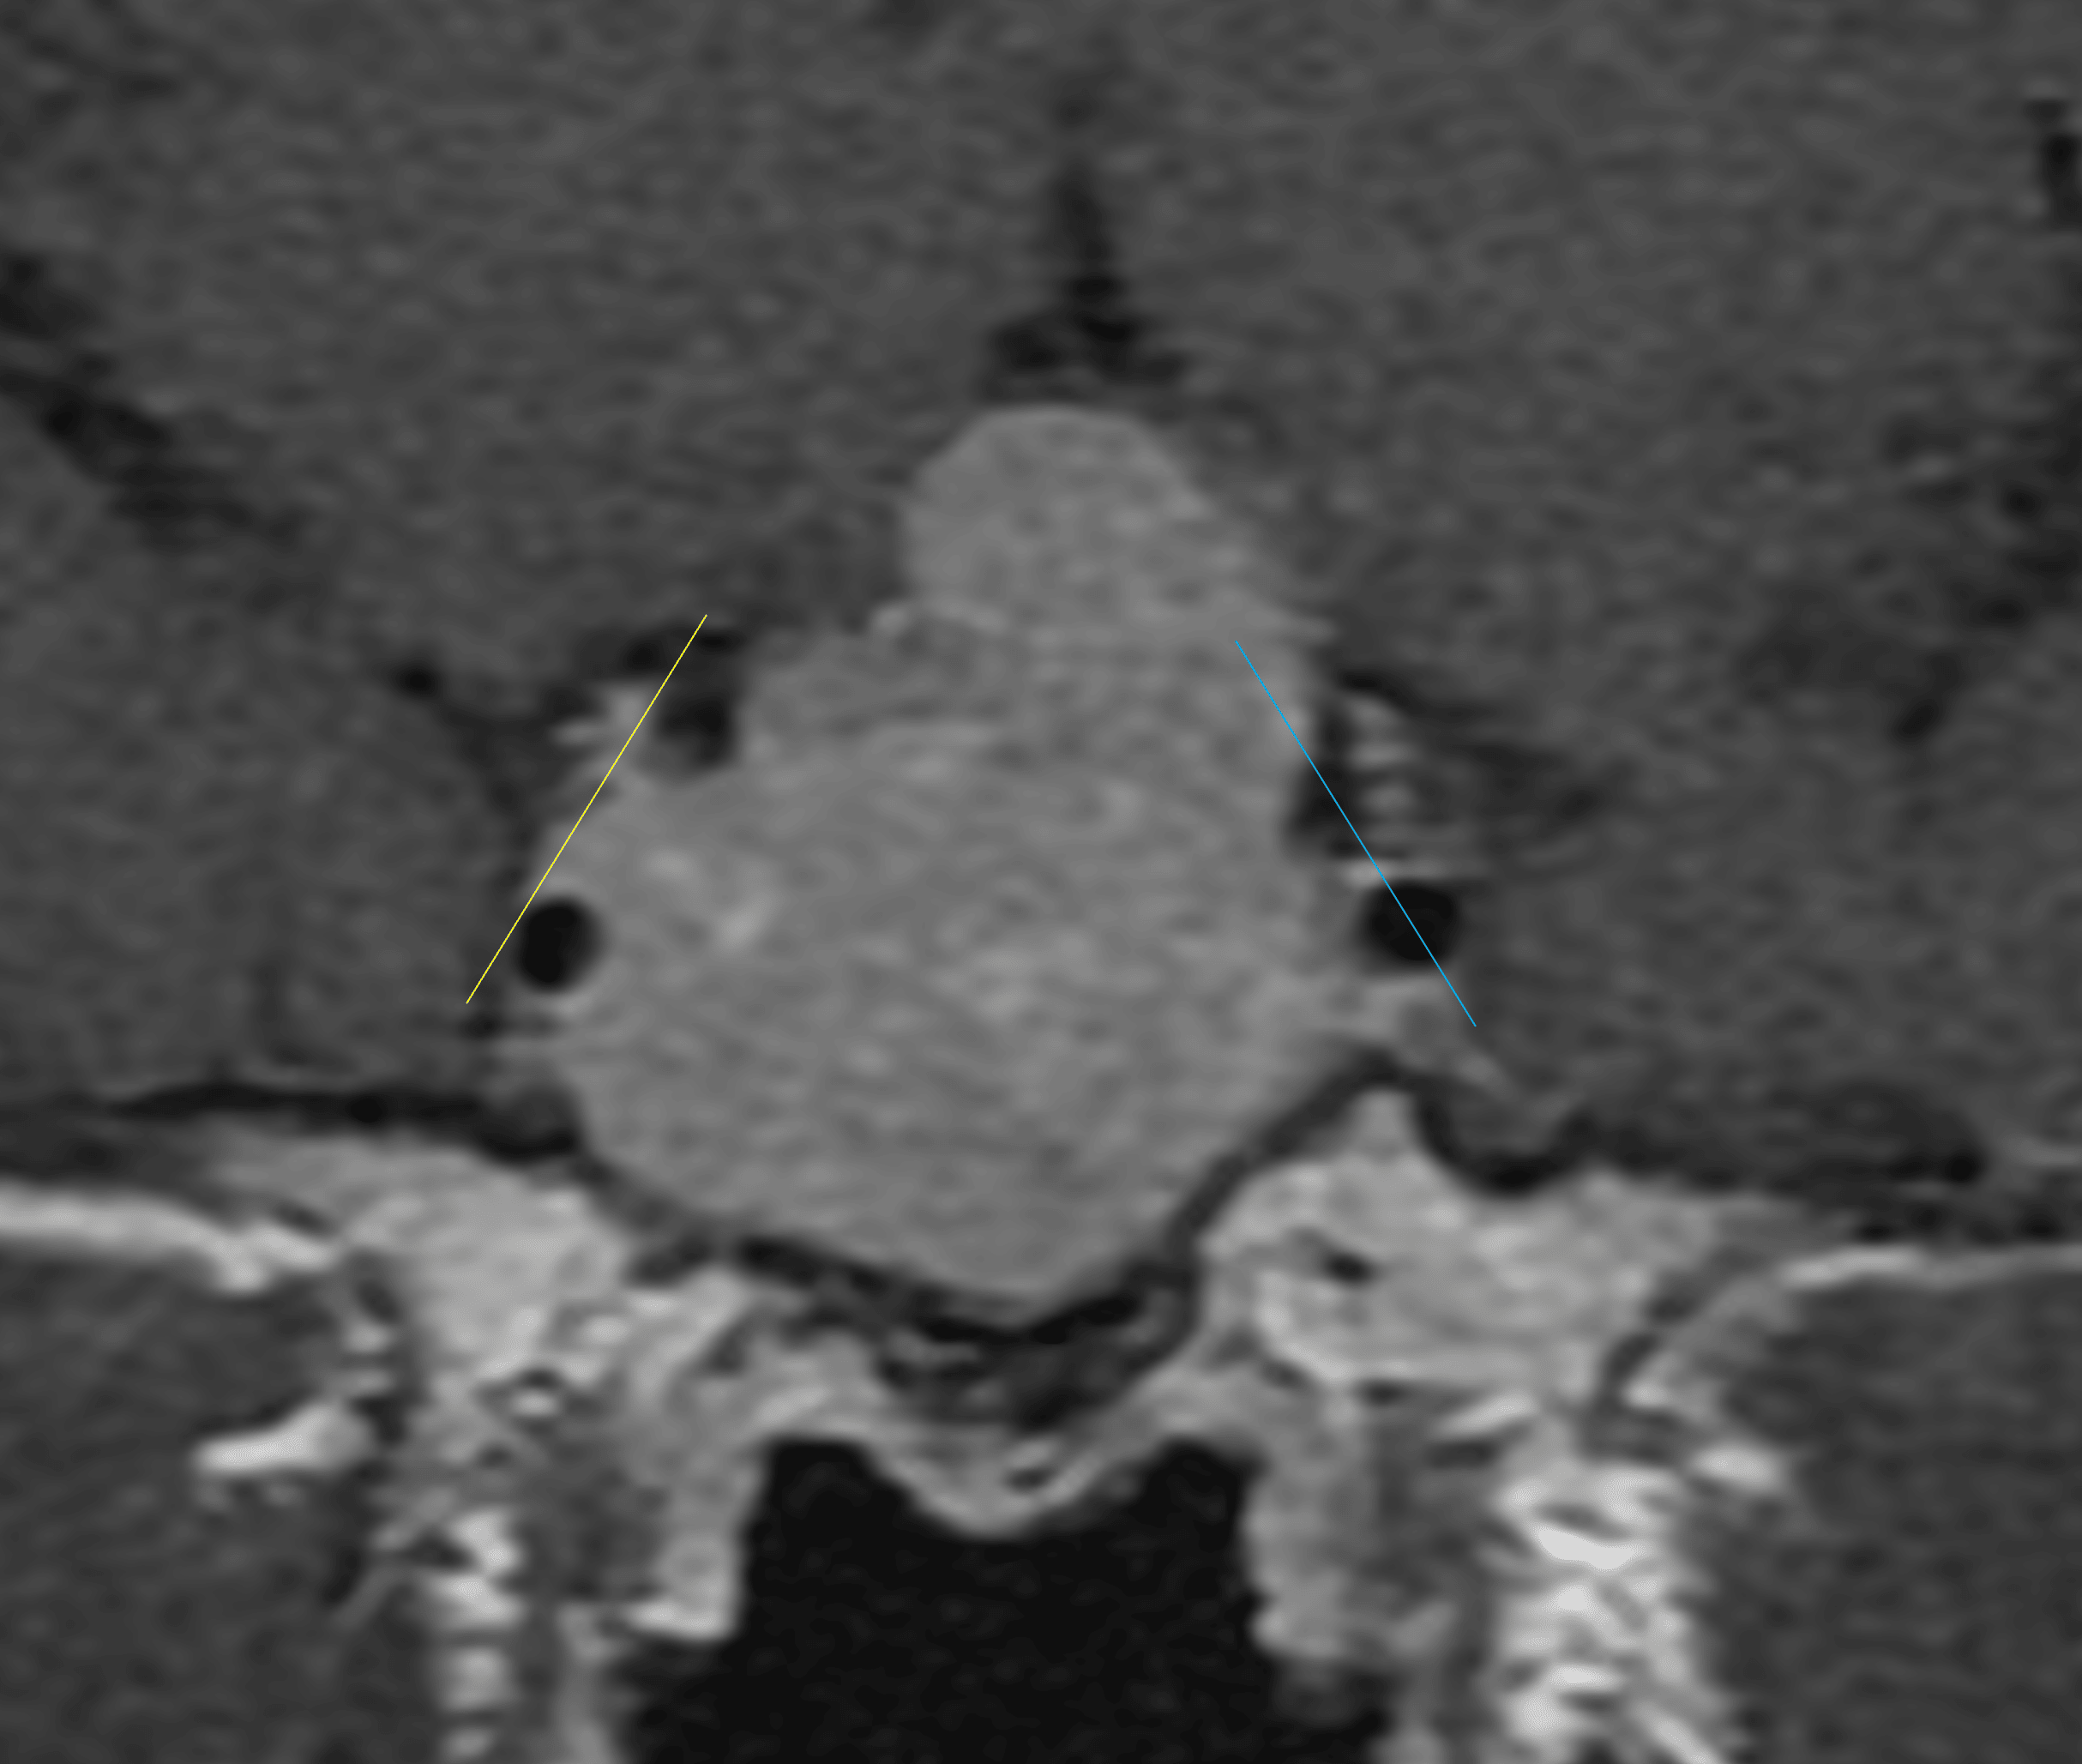

- Tumor extends beyond the lateral carotid tangent line on the right and slightly beyond the intercarotid line on the left with partial encasement of the bilateral internal carotid arteries

Tumor extends beyond the lateral tangent line on the right (yellow line) and the intercarotid line on the left (blue line).